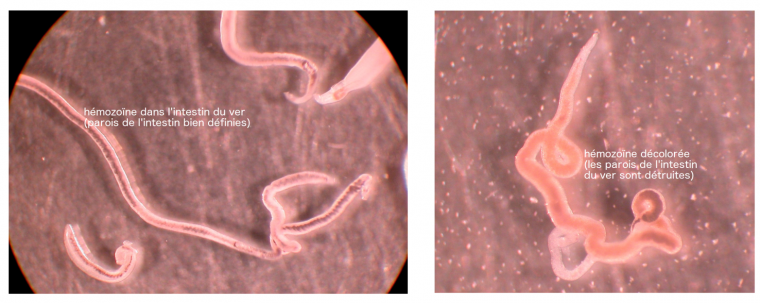

Les photos suivantes (Figure 19) montre la différence entre une femelle non traitée, avec de l’hémozoïne dans son intestin aux parois bien définies et une femelle traitée par PA1259.

Dans ce dernier cas, non seulement le ver est mort, mais l’hémozoïne est fortement décolorée, ce qui indique la destruction de cette molécule.1 Ce qu’il reste d’hémozoïne a aussi envahi le corps du ver, preuve de dégâts occasionnés à la paroi intestinale [9]. De l’hème alkylé par la trioxaquine est également présent chez les vers traités [9]. L’hémozoïne est donc bien, dans ce cas encore, une cible du médicament comportant un peroxyde. Cette trioxaquine est active également sur les stades larvaires de schistosomes.